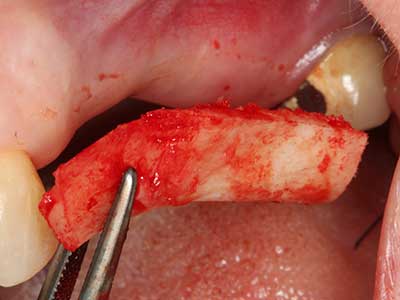

Aplicación: Obtención de hueso autógeno

Los injertos de hueso autógeno se utilizan en forma de bloques, escudillas, anillos y también se combinan con materiales de reemplazo óseo como virutas. Si el sitio del implante se prepara al mismo tiempo que el aumento, hay diversos sistemas de filtrado óseo que han demostrado su eficacia para la recopilación de las virutas óseas que se producen. Como alternativa, el sitio del implante se puede preparar usando un dispositivo de baja velocidad sin irrigación y si no se inserta ningún implante, es posible obtener virutas óseas de la periferia utilizando las rasquetas adecuadas. Esto también es posible aplicando cirugía piezoeléctrica con piezas especiales, y así se demostró en un estudio específico en el que se realizó una comparación directa con las virutas obtenidas con fresas redondas, ya que las virutas obtenidas con el método piezoeléctrico presentaron una mejor calidad (Chiriac, Herten et al. 2005).

En la extracción de bloques óseos la piezocirugía también presenta ventajas adicionales: Además de la alta precisión en la osteotomía que ya se ha descrito antes, se ha comprobado que el uso de los delgados insertos de sierra resulta especialmente cuidadosas con el hueso. Frente a esto, sobre todo cuando se usan las fresas de Lindemann, cabe esperar pérdidas en la extracción significativamente más altas debido al mayor grosor de la parte frontal del cabezal (Lakshmiganthan, Gokulanathan et al. 2012). La separación basal que se necesita en particular en los injertos de bloque extraídos de forma retromolar se ve facilitada mediante sierras perpendiculares especialmente previstas a tal fin, lo que permite considerar que la cirugía piezoeléctrica es un procedimiento preciso y seguro para la obtención de bloques de hueso en el área retromolar (Happe 2007) (fig. 1-12).